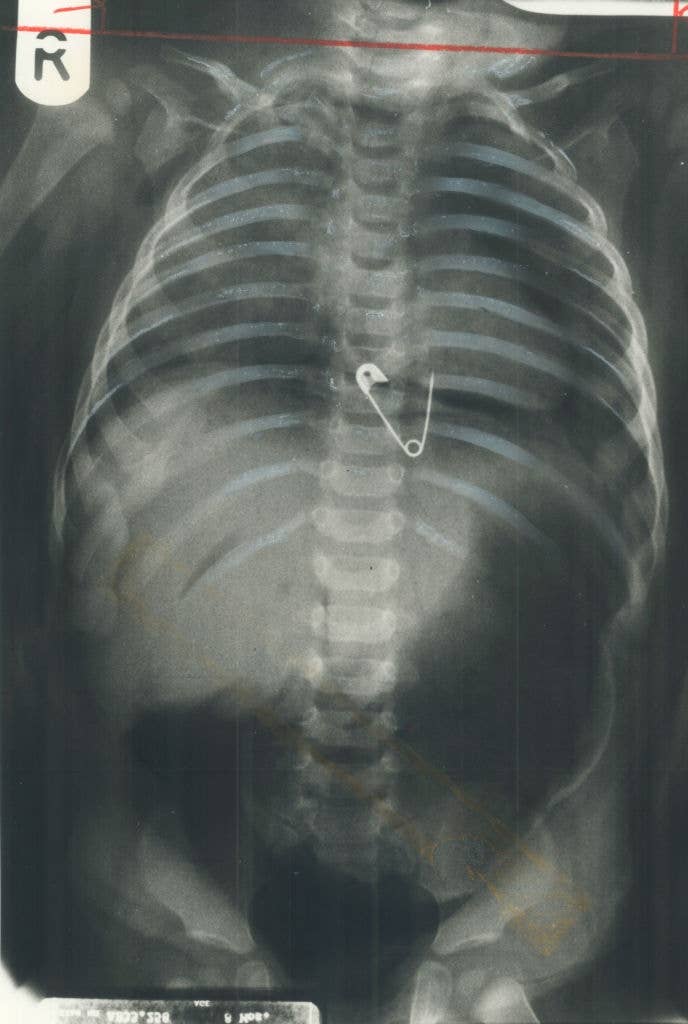

Surgeons, What's The Most Jaw-Dropping Thing You've Seen In The OR?

Be honest, is it actually wilder than Grey’s Anatomy? 👀